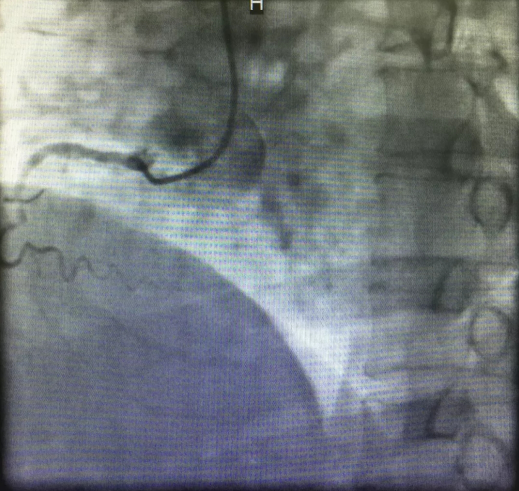

心内三完成成人导航首例逆向开通冠脉CTO病变